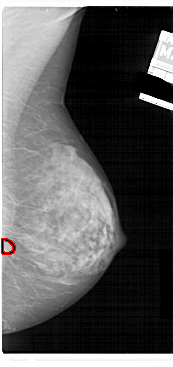

A_1912_1.RIGHT_CC

RIGHT_CC LINES 4531 PIXELS_PER_LINE 2356 BITS_PER_PIXEL 12 RESOLUTION 43.5 OVERLAY

FILE: A_1912_1.RIGHT_CC.OVERLAY

TOTAL_ABNORMALITIES 1

ABNORMALITY 1

LESION_TYPE MASS SHAPE OVAL MARGINS OBSCURED

ASSESSMENT 3

SUBTLETY 3

PATHOLOGY BENIGN

TOTAL_OUTLINES 1

BOUNDARY